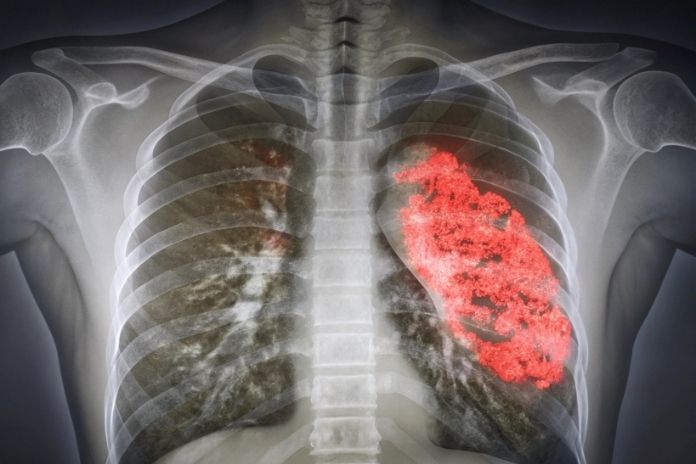

Pneumonia is an infection that inflames the air sacs in one or both lungs, which may fill with fluid or pus.

It can be caused by bacteria, viruses, or fungi, with bacterial pneumonia being the most common form. Symptoms typically include cough with phlegm, fever, chills, and difficulty breathing.